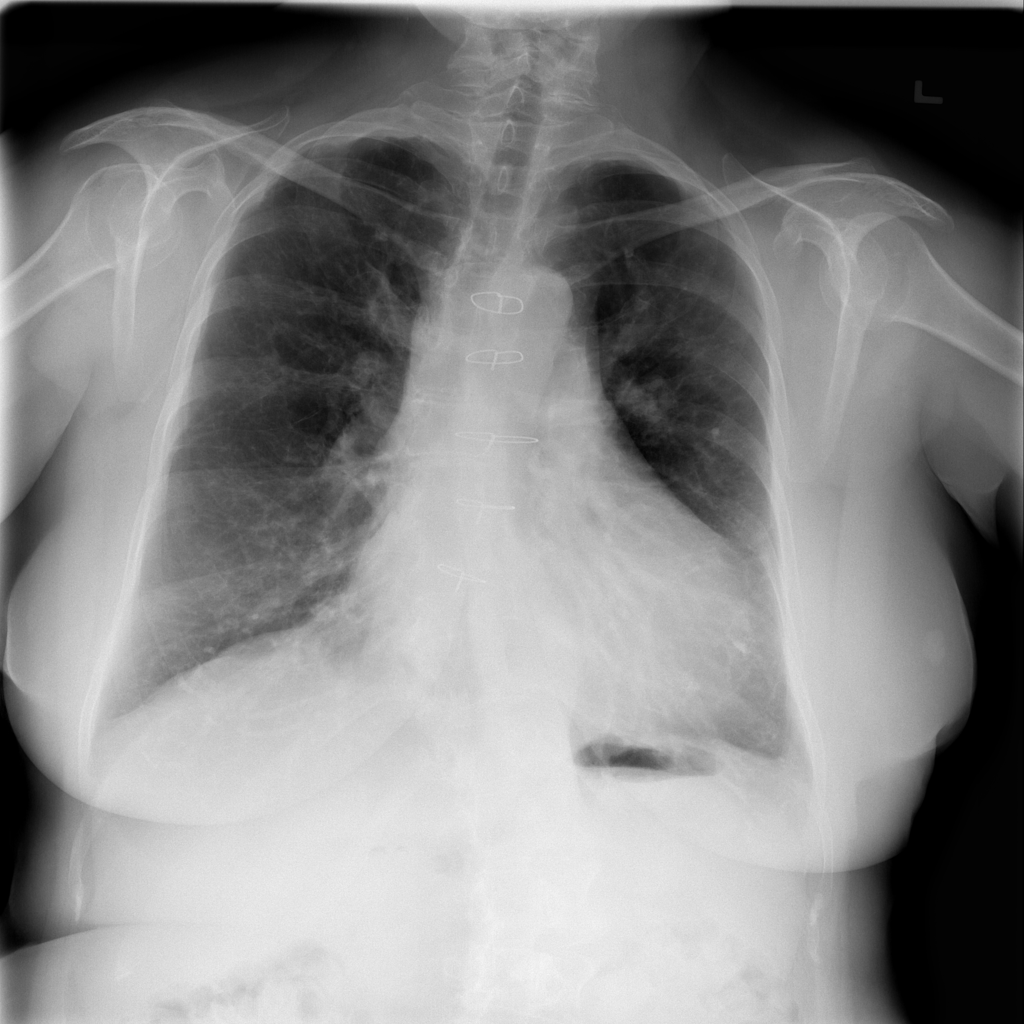

Cardiomegaly

Cardiomegaly means the heart appears enlarged on the chest X-ray. It is a descriptive imaging finding that can be related to heart strain, chronic pressure or volume changes, or even projection effects.

Showing up to 90 reference images for Cardiomegaly.

PAT-3384 · IMG-000Cardiomegaly

PAT-3384 · IMG-000

AP